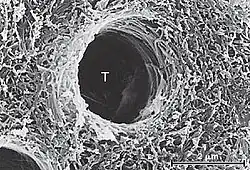

Smear layer refers to a layer of debris on the inorganic surface of substrate which comprises residual inorganic and organic components. This layer is produced whenever the tooth structure undergoes a preparation with a bur.[5]

Smear layer will fill the orifices of the dentinal tubules, hence forming smear plugs. These smear plugs decrease dentin permeability by 90% and the smear plug alone can prevent adhesive resin penetration into dentinal tubules. The thickness of smear layer can range from 0.5-2 μmeter and for the smear plug, 1 to 10 μmeter.[5]

Smear layer poses some threat for optimal bonding to occur. That is why it needs to be removed. For example, smear layer needs to be removed prior to bonding by etch-and-rinse (total etch) adhesives. This will lead to thicker hybrid layer and long, denser resin tags which results in better bond strength.[7]